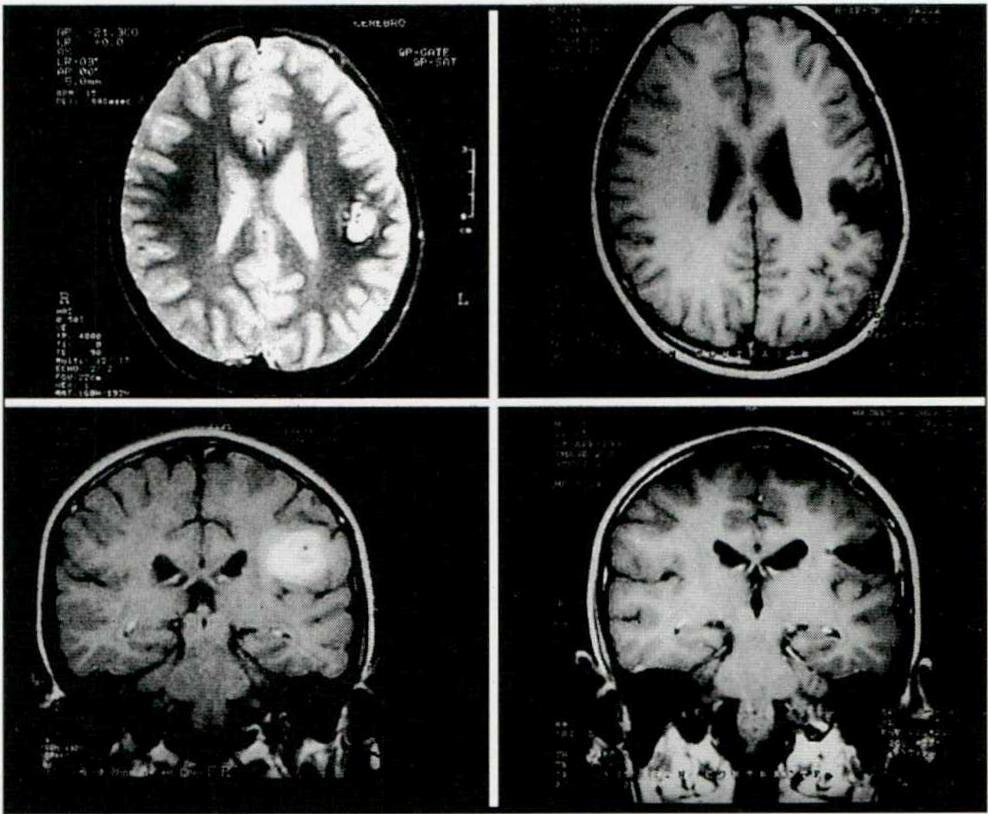

Es importante remarcar el aporte que significó el advenimiento de las nuevas técnicas electroencefalográficas en la selección del candidato a cirugía. Hacia fines de 1995 y comienzo del '96 se inauguraron en el país las primeras unidades de Video-telemetría, lo que mejoró y enriqueció el estudio de los candidatos. Esto permitió llegar a la cirugía con información suficiente para reducir el porcentaje de decisiones intraoperatorias, que dependían de la ECoG, con un potencial margen de error derivado del factor anestésico. La videotelemetría se efectuó en 47/68 (69,1%) de los pacientes. Los 21 pacientes operados sin Video-telemetría prequirúrgica tenían lesiones extensas con buen correlato con la clínica y el EEG prolongado computarizado (Fig. 1).

Fig. 1. Paciente varón de 9 años de edad, con crisis convulsivas mensuales. Los cortes axiales y coronales pre y postoperatorios de la IRM muestran un cavernoma del área central y su resección. Cuatro años de evolución postoperatoria sin crisis y sin secuelas